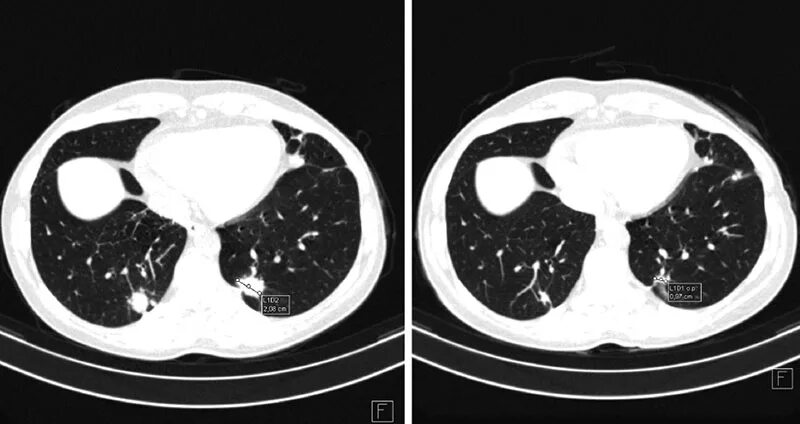

Рмж метастазы в легкие